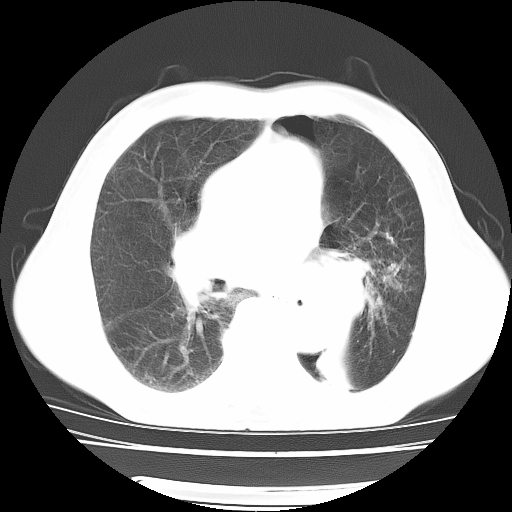

男,71岁,咳嗽,气喘10年,再发并咯血.胸片见气胸

考虑  左肺中心型肺癌伴阻塞性肺炎,肺不张,纵膈淋巴结肿大。慢支炎,肺气肿,左侧气胸肺压缩5%

左侧中央型肺癌伴纵膈淋巴结转移。

左肺中心型肺癌伴阻塞性肺炎,肺不张,纵膈淋巴结肿大

1)考虑左肺中心型肺癌伴阻塞性肺炎、左肺下叶肺不张、左侧肺气肿,纵膈淋巴结转移。2)左侧气胸(肺组织压缩约5%)。

左肺中心型肺癌伴阻塞性肺不张、肺气肿 。

1)考虑左肺中心型肺癌伴阻塞性肺炎、左肺下叶肺不张、左侧肺气肿,纵膈淋巴结转移。2)左侧气胸。